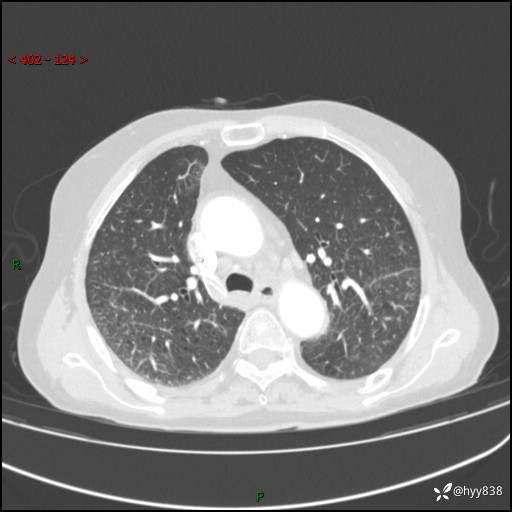

胸部CT增强(外院平扫)